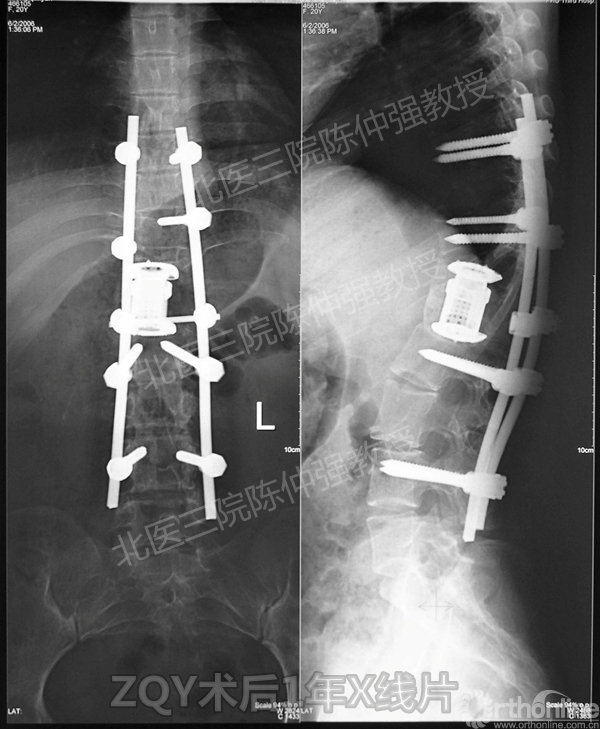

ZQY术后1年

患者女性17岁,胸腰椎陈旧结核性侧后凸畸形,局部呈“麻花状”扭转,无神经功能受损表现。2005年,陈仲强教授带领团队实施后路+侧前方联合入路脊柱节段切除、双轴旋转矫形术。术后患者外观显著改善,神经功能正常。术后随访证实患者截骨矫形节段骨性融合良好,矫形效果持续良好。